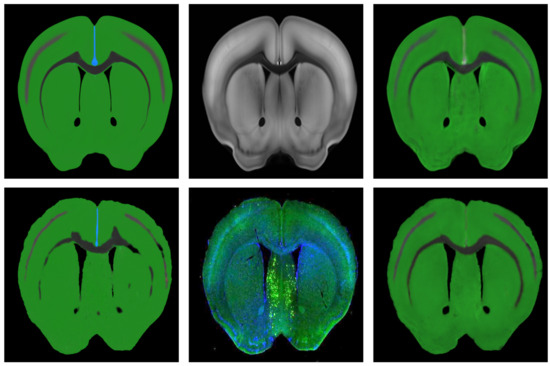

3.4. Performance Evaluation

After the optimal spatial deformation field is obtained, the spatial transformation layer can be used to apply the spatial deformation field to the ADA to evaluate the performance of the registration results. The ADA has rich regional division information, and different brain regions are separated by different colors. Thus, the edges of regions can be easily extracted, and then the edges of the regions are fused with the brain slices to complete the localization of the regions in the mouse brain slices. The performance of different methods was compared with the accuracy of localization, and the results are shown in Figure 5.

According to the fusion effect of images, the results of the regional localization method in this study were noticeably better than others. The external edge and internal feature contour fit well with the brain slice images, and the original topological structure was left unchanged. The regional localization effect of some brain slices is shown in Figure 12.

Figure 12. Five examples of regional localization of the brain slice. (a) is the original brain slice; (b,c) represent the ADA and its deformation after registration, and (d) shows the fusion of the edge contour of (c) and the image of (a).